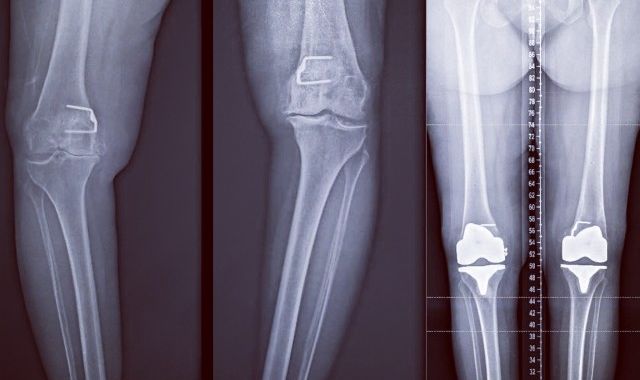

Naturally Aligned Computer Assisted Knee Replacement

Computer assisted Surgery (CAS) has now been around for almost 20 yrs. in various forms. With the...

Alternate Alignment Technique for Total Knee Replacement

Alternate alignment is gaining popularity amongst orthopaedic surgeons. The alternate alignment...

Alternate Knee Alignment Technique - Dr Kaushik Hazratwala

It is important to understand that there are multiple bony cuts that are delicately balanced with...

Computer assisted Knee Arthroplasty - Dr. Kaushik Hazratwala

Knee replacements have been traditionally been done by bony alignment jigs. That is the surgeon...